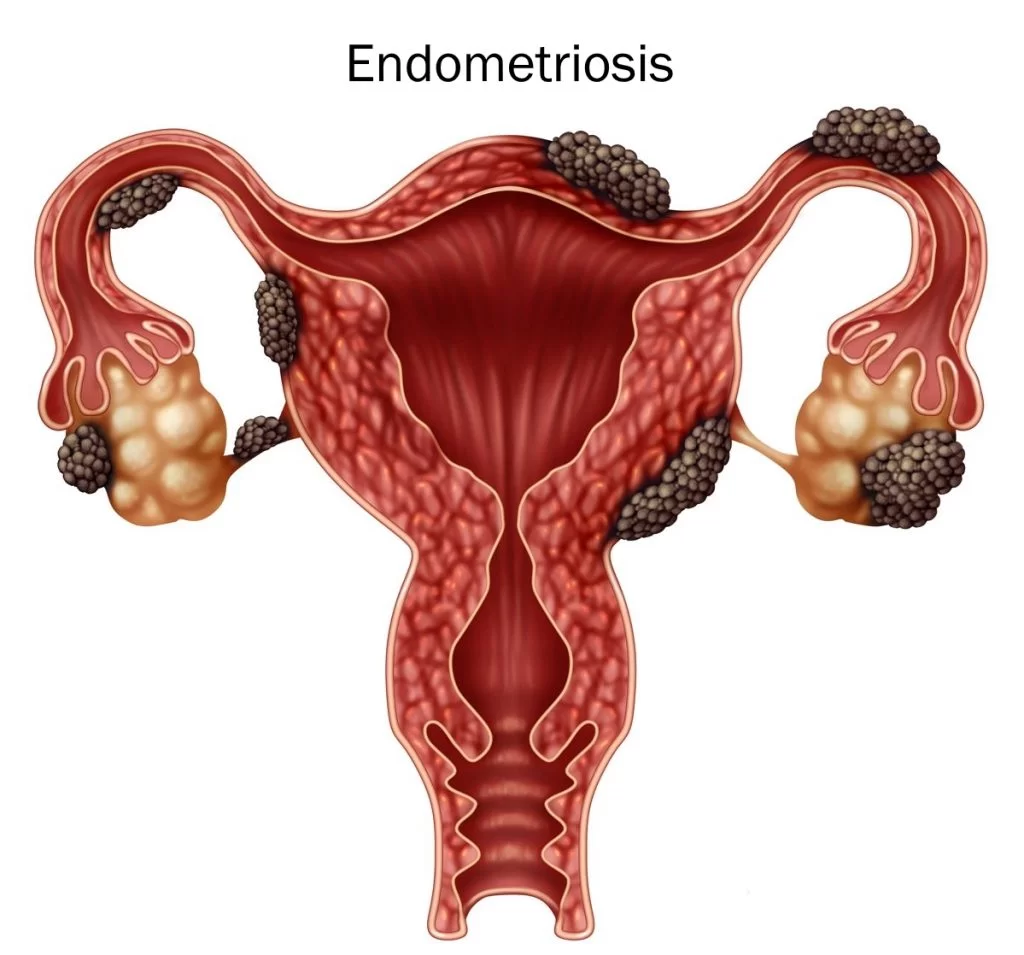

कारण 4: एंडोमेट्रियोसिस – जब अंदर की परत गलत जगह पहुंच जाए

एंडोमेट्रियोसिस एक ऐसी स्थिति है जिसमें गर्भाशय की अंदरूनी परत जैसी कोशिकाएं गर्भाशय के बाहर बढ़ने लगती हैं। ये कोशिकाएं भी हर महीने हार्मोन के प्रभाव में सूजती और खून बहाती हैं, लेकिन क्योंकि वे बाहर होती हैं, इसलिए यह खून बाहर नहीं निकल पाता।

इस वजह से शरीर के अंदर सूजन, दर्द और ज्यादा ब्लीडिंग जैसी समस्याएं पैदा होती हैं। एंडोमेट्रियोसिस में पीरियड्स बेहद दर्दनाक हो सकते हैं और ब्लीडिंग असामान्य रूप से ज्यादा हो सकती है।

यह समस्या अक्सर सालों तक पहचान में नहीं आती, क्योंकि महिलाएं दर्द को सामान्य समझकर सहती रहती हैं।